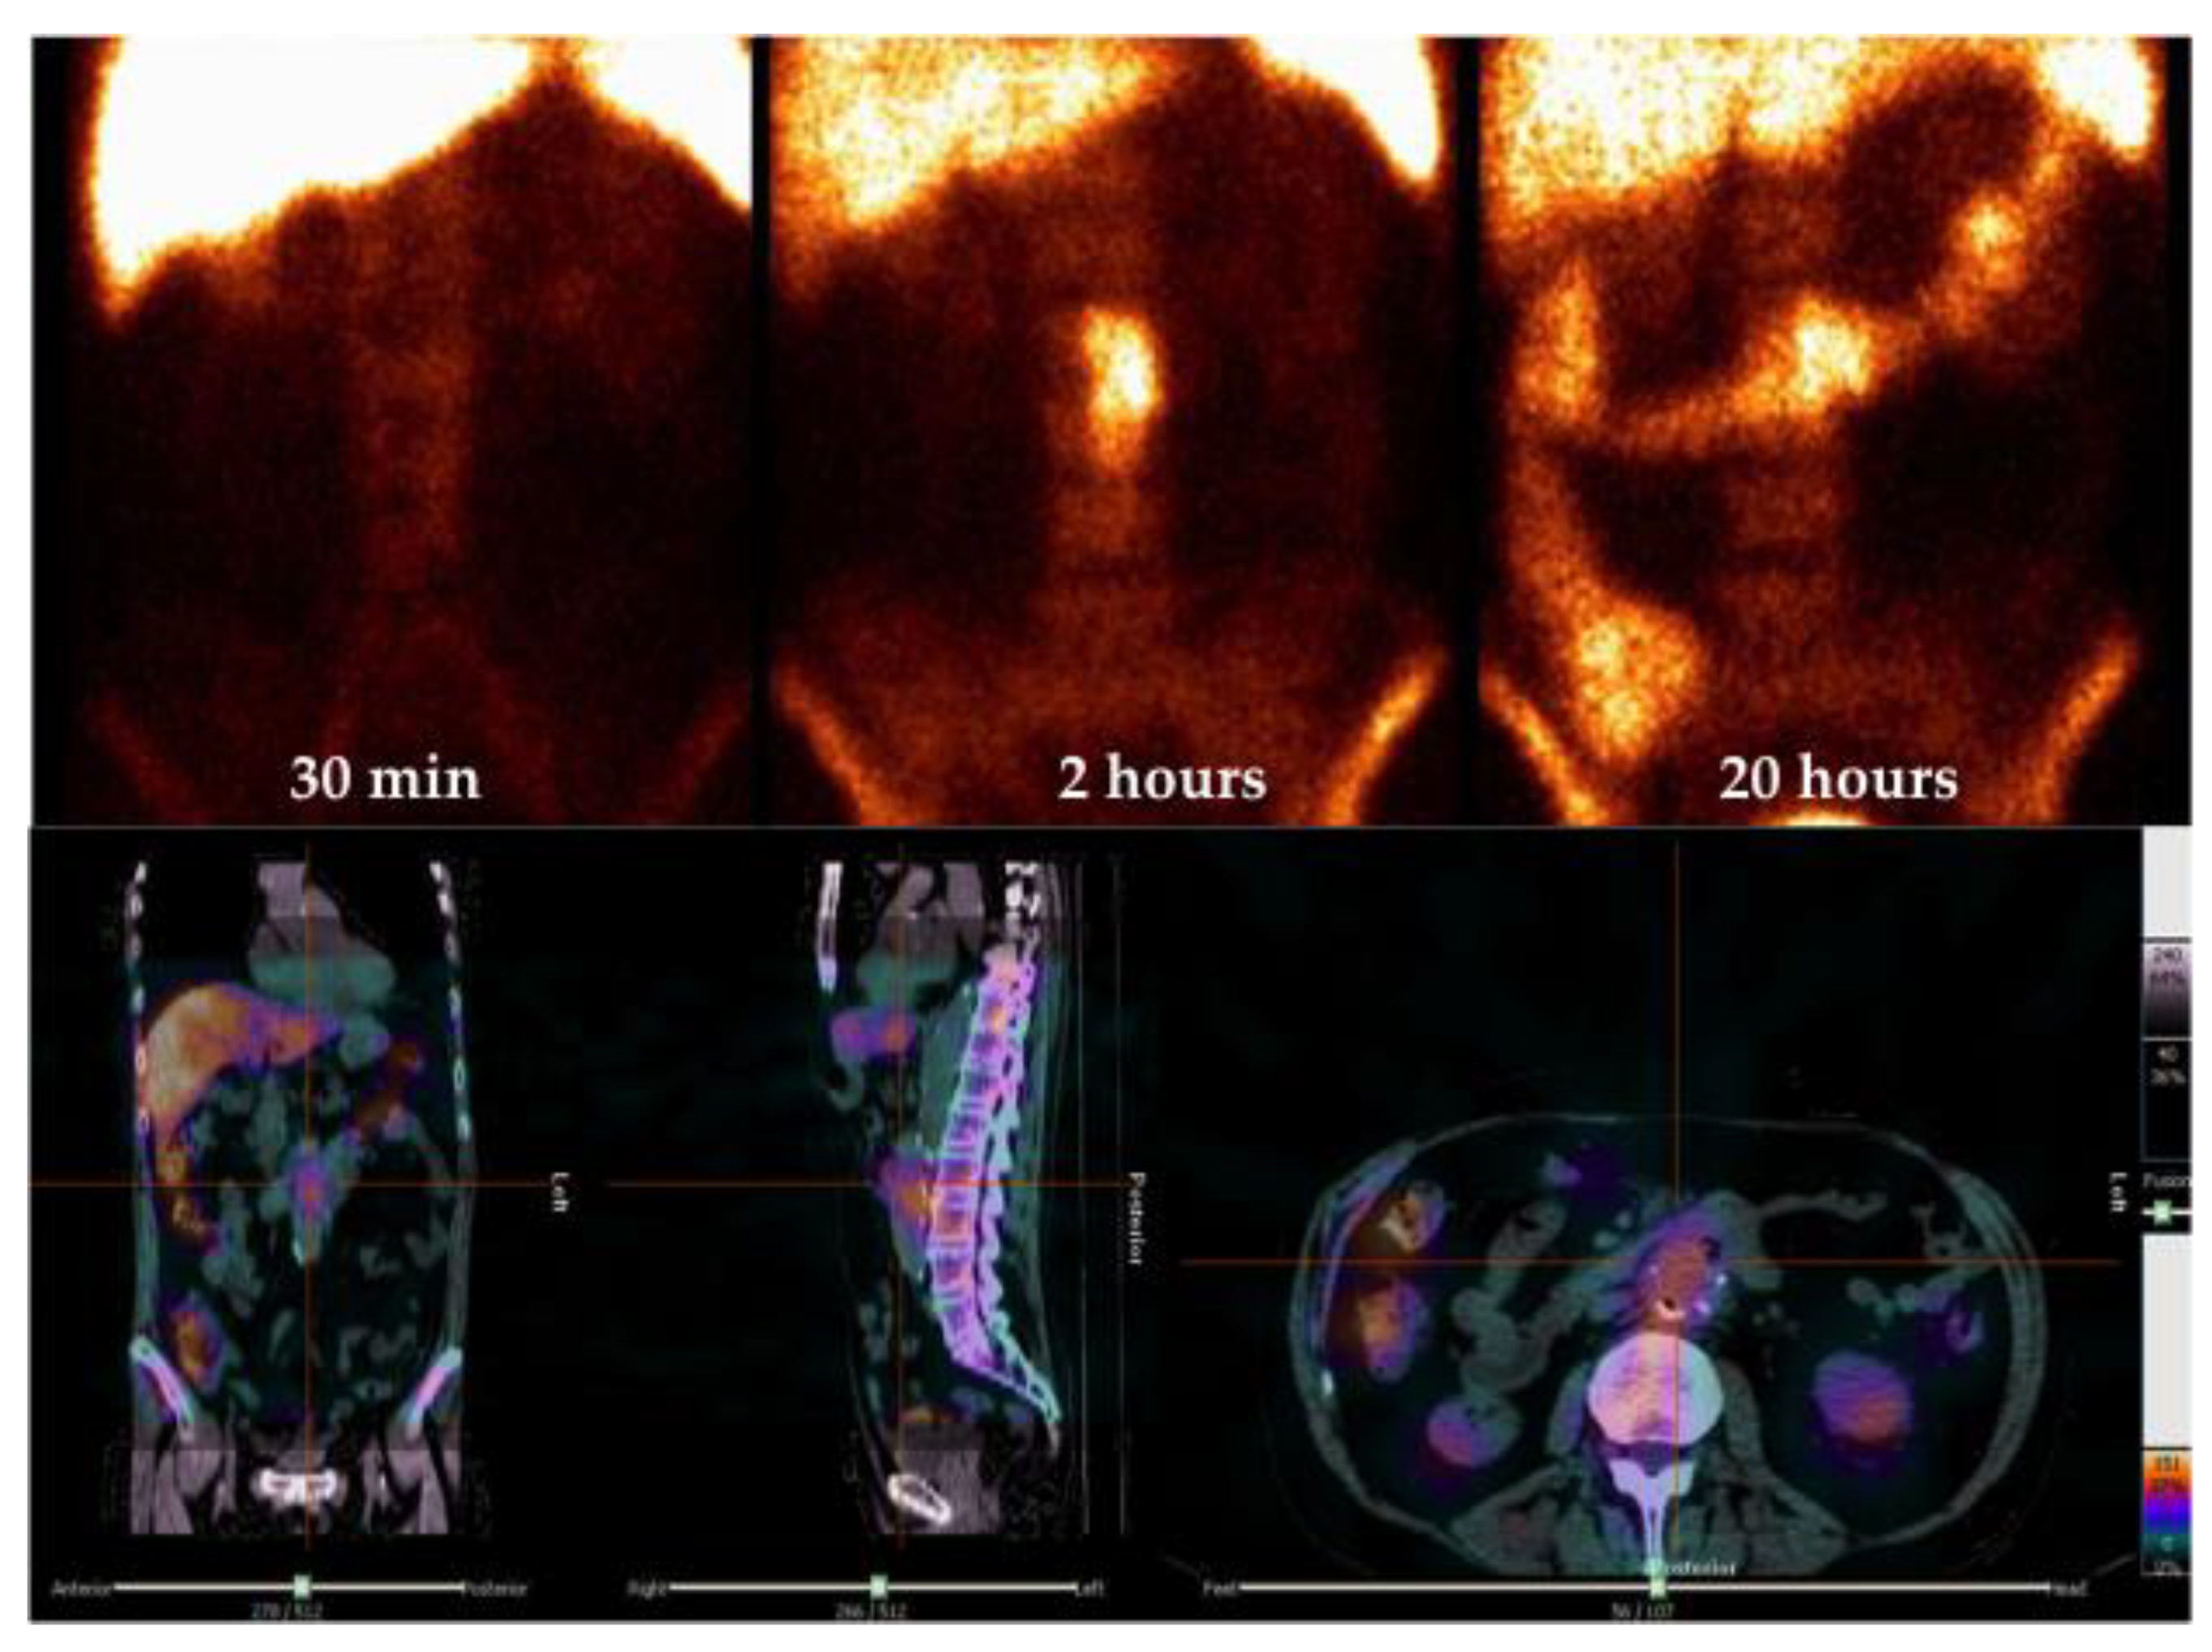

4.1. Gamma-Camera Imaging for VGI

4.2. [18F]FDG PET/CT Imaging of VGI